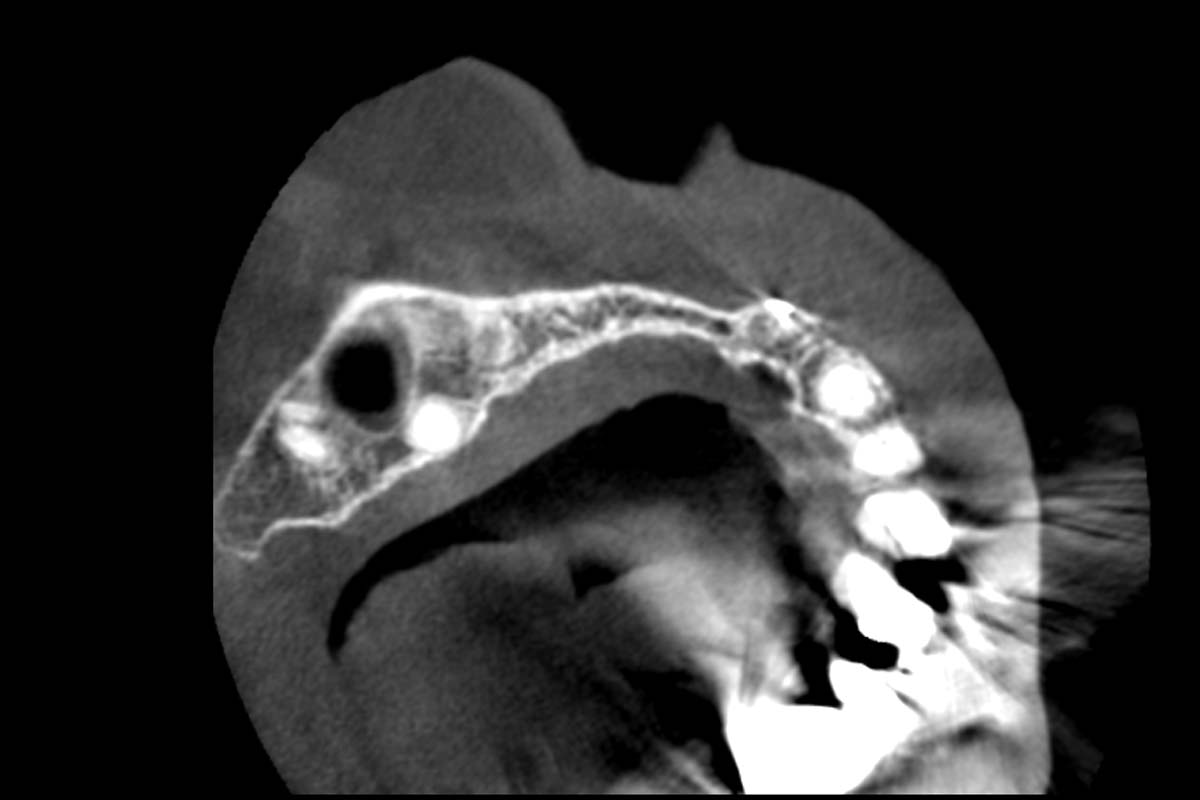

Initial x-ray, ten years post implantationem alio loco, large peri-implant bone loss

Initial CBCT scan - Fracture of left maxillary incisor and loss of buccal wall